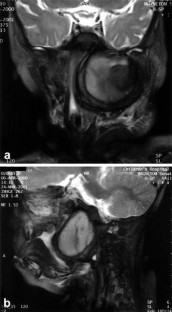

Giant mycotic aneurysm of the internal carotid artery in a child: endovascular treatment

We present a case of a giant mycotic aneurysm of the left internal carotid artery in a child, the result of direct extension of a deep neck space infection. This lesion is life threatening and may put the patient at risk of unwarranted biopsy or drainage if not recognized. Diagnosis and treatment planning rely heavily on cross-sectional imaging, and angiography is frequently necessary. This case is unique for two reasons: (1) we present for the first time the MRI findings and (2) we describe an alternative to surgical ligation -- neurointerventional embolotherapy. Minimally invasive transcatheter embolization was successfully performed on our patient to occlude the abnormal left internal carotid artery segment.

Fig. 1.

Fig. 2.